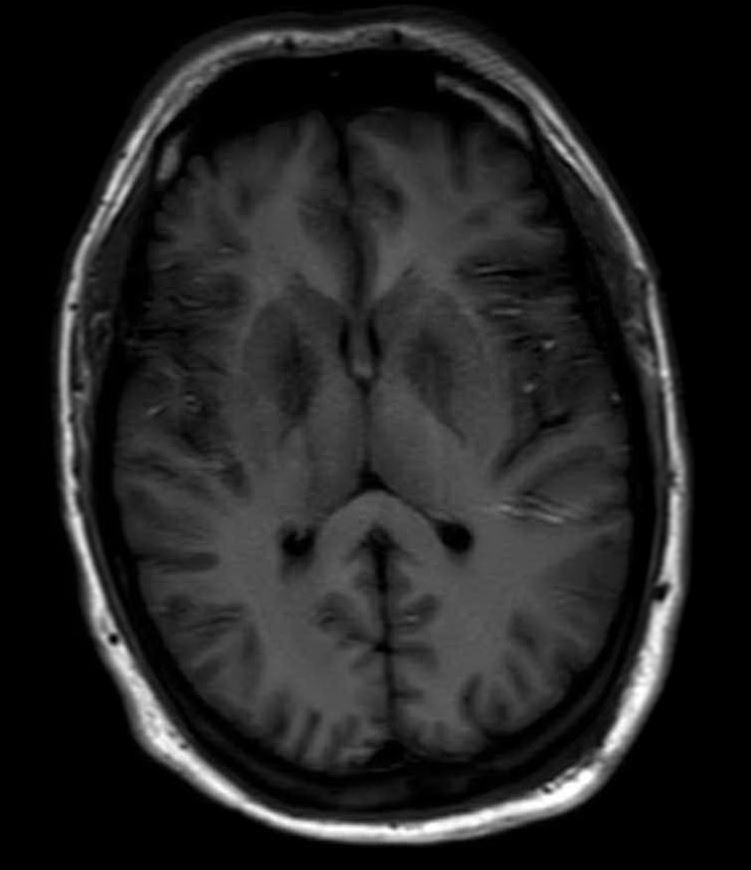

Carbon Monoxide (CO) is one of the leading causes of poison deaths in the United States. Signs and symptoms are clinically variable secondary to inconsistent targeting of highly metabolic tissues by the gas. We report a case of a man in his early to mid-30's presenting to the emergency department with mental status changes, fatigue, headache, and flu-like symptoms for three days. The patient had been working on his motor vehicles in the garage during this time, using a portable diesel powered space heater to keep warm. Subsequent neurology and cardiology workup demonstrated bilateral globus pallidus (GP) lesions on brain imaging, increased non-myocardial infarction troponin levels, carboxyhemoglobin (COHb) level of 3.8%, elevated liver enzymes, and acute kidney failure. In this setting of his delayed presentation as a smoker with carbon monoxide poisoning, carboxyhemoglobin levels alone become less reliable. This report investigates the use of bilateral GP lesions, the most frequently affected structure, as well as damage preference to highly metabolic tissues to assist in diagnosis and prognosis for CO poisoning. Our observations can be used for further study of the relationship between bilateral GP necrosis and initial presentation and outcome of patients experiencing CO poisoning leading to earlier recognition, treatment, and decreased morbidity/mortality.

一氧化碳(CO)是美国中毒死亡的主要原因之一。由于该气体对高代谢组织的靶向作用不一致,其体征和症状在临床上具有变异性。我们报告一例30岁出头至35岁左右的男性病例,该患者因精神状态改变、疲劳、头痛及类似流感症状三天而就诊于急诊科。在此期间,患者一直在车库里修理他的机动车,使用便携式柴油动力取暖器取暖。随后的神经科和心脏科检查显示,脑部成像有双侧苍白球(GP)病变,非心肌梗死肌钙蛋白水平升高,碳氧血红蛋白(COHb)水平为3.8%,肝酶升高,以及急性肾衰竭。在该吸烟者一氧化碳中毒延迟就诊的情况下,仅碳氧血红蛋白水平变得不太可靠。本报告探讨了使用双侧GP病变(最常受影响的结构)以及对高代谢组织的损伤偏好来辅助一氧化碳中毒的诊断和预后评估。我们的观察结果可用于进一步研究双侧GP坏死与一氧化碳中毒患者的初始表现及预后之间的关系,从而实现早期识别、治疗并降低发病率/死亡率。